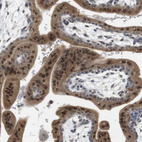

Immunohistochemical staining of human placenta shows strong nuclear positivity in trophoblastic cells.